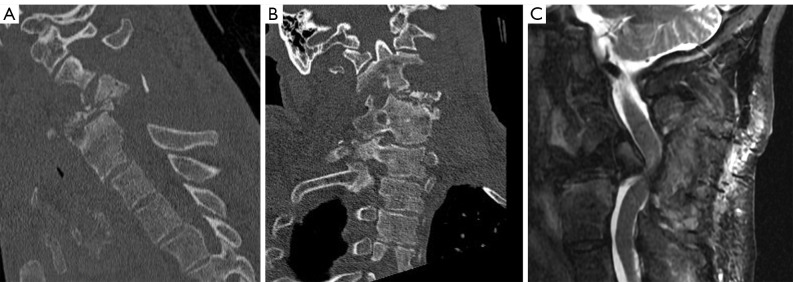

Case description: We present a medically complex 58-year-old male who developed a severe combined kyphotic and coronal cervical deformity in a delayed fashion after an initial posterior cervical decompression for symptomatic epidural abscess associated with VO. The patient underwent a combined two-stage anterior and posterior approach. The patient tolerated both surgeries without complication and follow-up imaging demonstrated correction of cervical sagittal and coronal alignment. Interestingly, despite appropriate antibiotic therapy, intraoperative culture during deformity correction yielded growth of the initial culprit microorganism.

Conclusions: A two-stage anterior and posterior approach with multi-level anterior cervical decompression and instrumented fusion followed by posterior cervicothoracic instrumented fusion addresses the primary surgical goals of affected spinal segment decompression, restoration of appropriate spinal alignment, and prevention of further deformity or neurologic compromise. This report highlights suitability of techniques accessible to most spinal surgeons for correction of a multiplanar deformity, contributes to the ongoing discussion regarding instrumentation in the setting of an active spinal infection, and emphasizes the importance of close clinical and radiographic follow-up in this patient population.